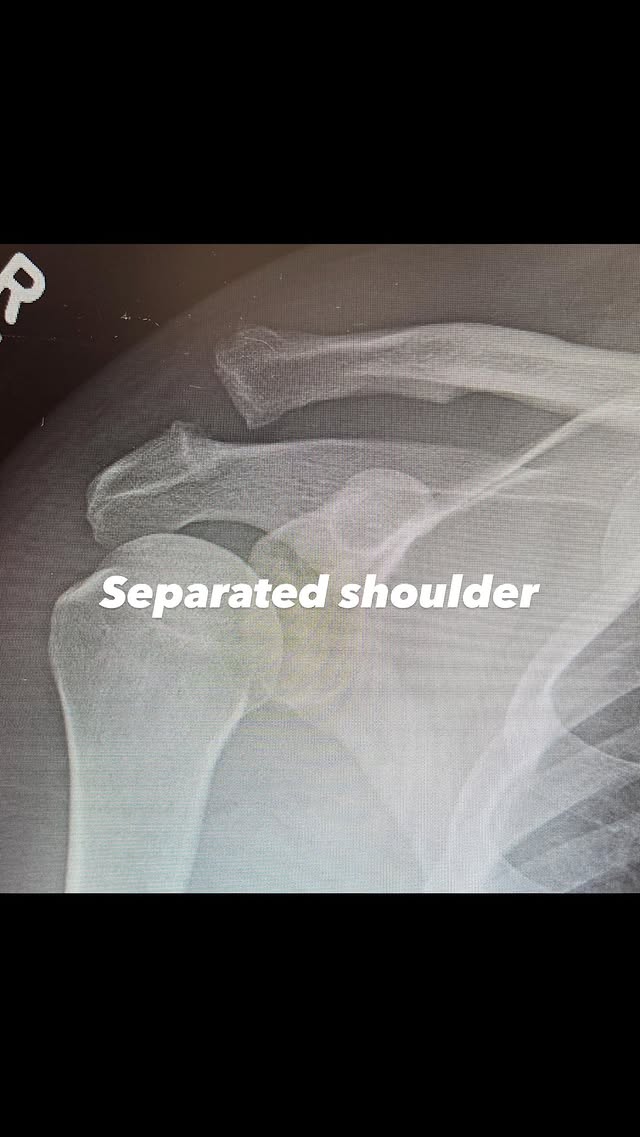

Στην πρώτη ανάρτηση, ο Tatum μοιράστηκε μια ακτινογραφία του άνω βραχίονα και της περιοχής του ώμου, όπου ήταν εμφανές ότι δύο οστά ήταν σπασμένα.

«Αποκόλληση ώμου», έγραψε, ακολουθούμενο από μια δεύτερη φωτογραφία μετά την επέμβαση στο ίδιο σημείο.